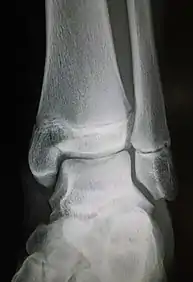

Fracture of the medial malleolus seen on X-ray scan (left ankle)

Common symptoms of a Maisonneuve fracture are pain, swelling, tenderness, and bruising around the ankle joint and inferior (or distal) tibiofibular joint. More specifically, as a pronation-external rotation injury, pain during external rotation of the ankle joint is expected. Additionally, there is a reduced range of motion of the foot and an inability to weight-bear due to ankle pain.[4][7] Pain may also be felt around the medial and lateral aspects of the ankle, and more rarely around the superior (or proximal) tibiofibular joint.[9] Damage to the deltoid ligament or interosseous membrane can cause haemorrhaging around the surrounding tissues, resulting in a localised oedema.[8]

Fracture of the lateral malleolus seen on X-ray scan (left ankle)